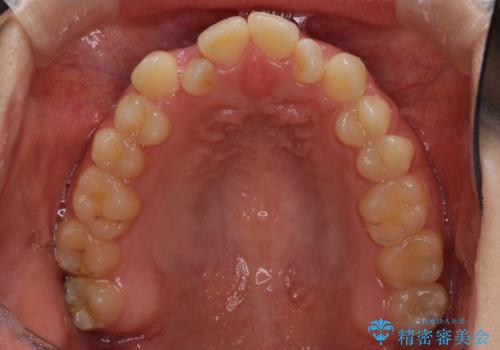

- 前歯のデコボコと、下顎の変位と受け口を気にして来院された患者様です。

初診時には大学病院にて顎の骨を切る外科矯正を勧めましたが、妥協的なゴールでも構わないので外科処置をせずに矯正を行いたいとのことでした。

まずは急速拡大装置にて上顎骨を側方に拡大し、インビザラインにて歯列と咬合を整えることとしました。